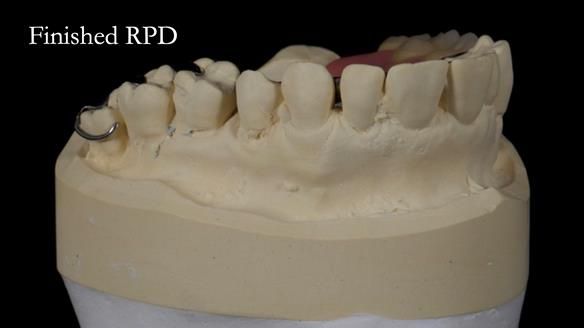

Welcome to Newsletter 64. I'll walk you through the process of providing a Mk 2 metal-based partial denture (RPD), for Ian a retired Veterinary Surgeon aged 78. The RPD was made at an increased vertical dimension and acted as an occlusal stabilisation splint - reducing the wear and bite force on the remaining natural teeth.